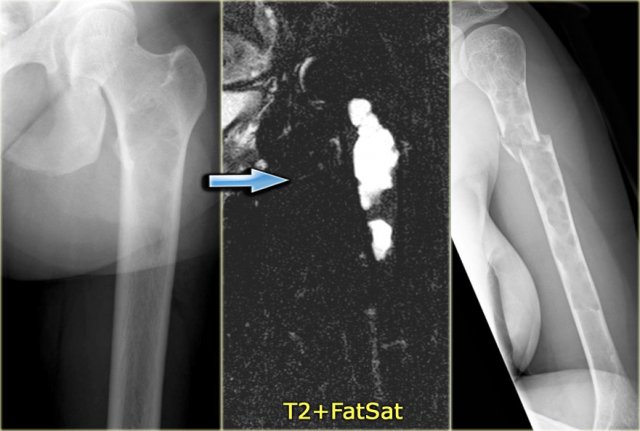

Fibrous dysplasia (6)

On the left images of a patient with polyostotic FD.

On the far left a well-defined lytic lesion with groundglass appearance in the proximal femur diaphysis, consistent with fibrous dysplasia.

T2-weighted MR image with FS reveals cytic degeneration of the fibrous dysplasia, which is a common finding.

This patient has a second lesion in the shaft of the humerus witha pathologic fracture.